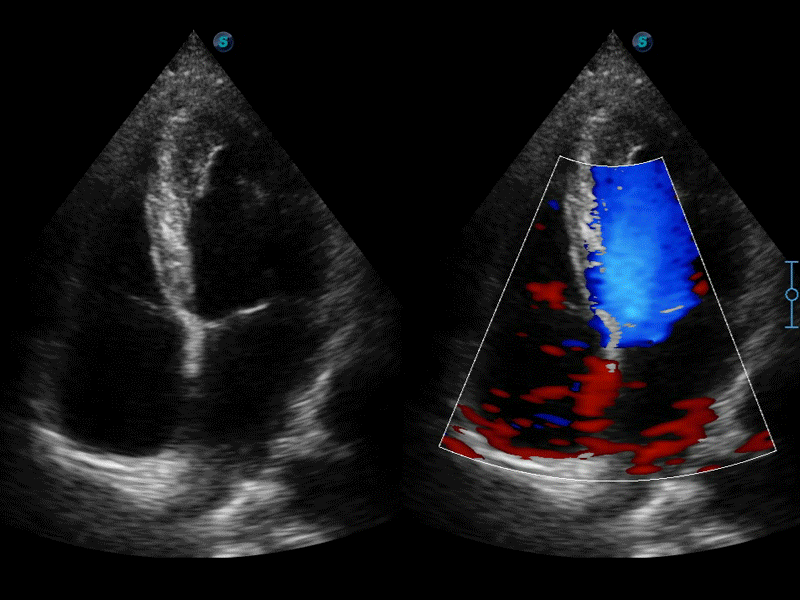

自动识别收缩和舒张末期心肌内膜,自动计算射血分数EF值。